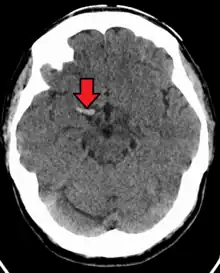

CT scan without intravenous contrast showing hyperdense aspect of the right middle cerebral artery, indicating thrombus within the vessel

In medicine, the dense artery sign or hyperdense artery sign is an increased radiodensity of an artery as seen on computer tomography (CT) scans, and is a radiologic sign of early ischemic stroke.[1] In earlier studies of medical imaging in patients with strokes, it was the earliest sign of ischemic stroke in a significant minority of cases.[2] Its appearance portends a poor prognosis for the patient.[3][4]

The sign has been observed in the middle cerebral artery (MCA),[4] posterior cerebral artery (PCA),[5] vertebral artery,[2] and basilar artery;[6] these have been called the dense MCA sign, dense PCA sign, dense vertebral artery sign, and dense basilar artery sign, respectively.